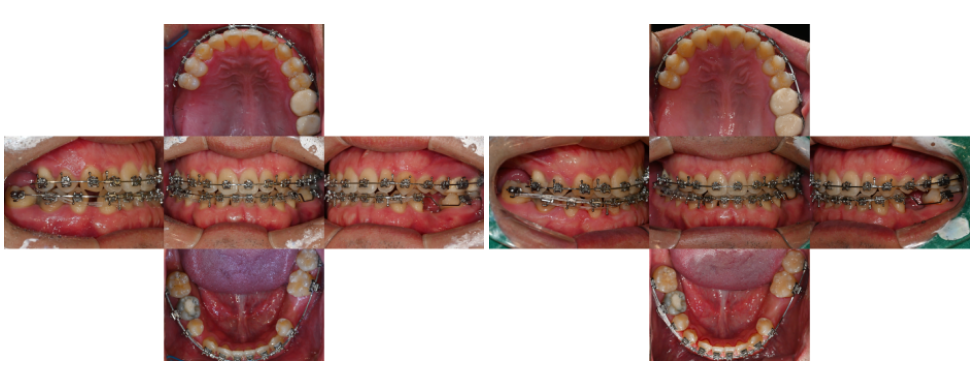

24.08.19//25.01.13

교정 치료 과정에서

반대교합을 동시에 개선하면서

임플란트 식립을 위한 공간을

확보하게 됩니다.

필요에 따라 치간이개를 조절하고

전체적인 치아 배열을 정리해요.

골격적 문제가 심한 경우에는

악교정 수술을 병행하기도 합니다.

주걱턱이 심한 경우 수술적 교정을

통해 턱의 위치를 개선한 후

치아 배열을 정리하는 방식으로

진행될 수 있어요.